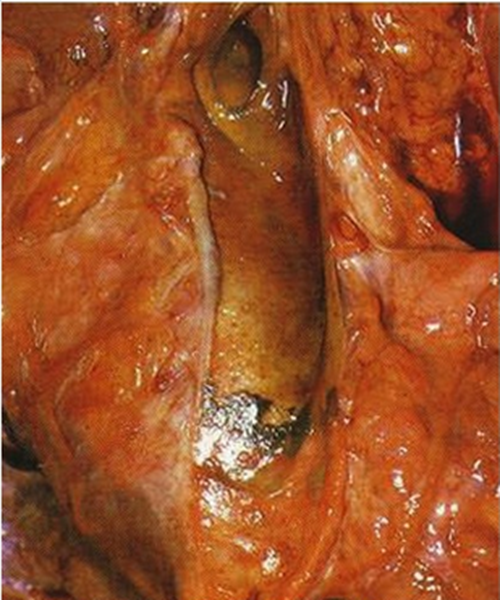

膽管癌圖片

內膽管癌早期症狀

肝內膽管癌晚期症狀

肝內膽管癌末期

肝內膽管癌

肝內膽管癌後期症狀